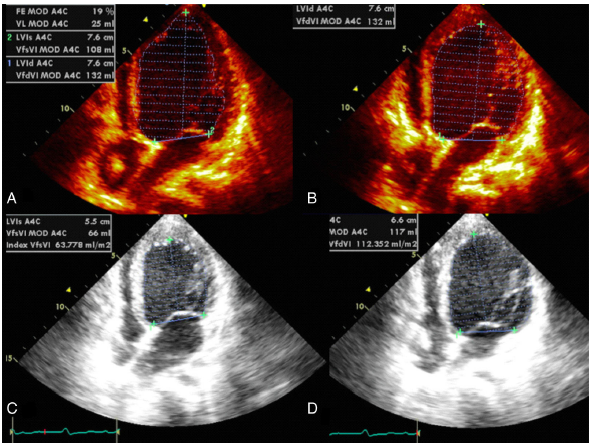

El ecocardiograma transtorácico confirmó un severo compromiso de la función sistólica y diastólica ventricular izquierda (FEVI: 18%), dilatación ventricular izquierda (VFsVI 108 mL, VFdVI: 132 mL). No se observó corto circuito residual. Se documentó movimiento paradójico del septum.

Figura 2 Valoración ecocardiográfica preoperatoria (A-B) y postoperatoria (C-D); se aprecia cambio significativo en los volúmenes de fin de diástole y de sístole y por consiguiente de la fracción de eyección, pasando de 18 a 43%. A) VfsVI A4C 108 ml. B) VfdVI 132 ml. FEVI: 18%, por Simpson biplano. Posterior a la resincronización: C) VfsVI A4C 66 ml. D) VfdVI A4C 112 ml, FEVI 43% por Simpson biplano. VfsVI (Volumen de fin de sístole ventrículo izquierdo), VfdVI (volumen de fin de diástole ventrículo izquierdo).